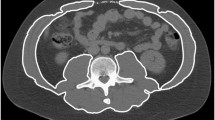

We included 107 healthy Caucasian patients (46 males; 61 females) with a healthy BMI (18–25 kg/m2) for analysis. Body composition data were obtained from a single transverse CT image at the mid-third lumbar vertebrae using ImageJ software. Tissue segmentation was performed using Hounsfield unit thresholds of −29 to +150 for muscle and −190 to −30 for adipose tissue.

CT scans were assessed for quality as previously described [16]. Data were obtained from a transverse CT image at the mid-third lumbar vertebrae using ImageJ software (National Institute of Health, Bethesda, MD, USA). Tissue segmentation was performed using Hounsfield unit thresholds of −29 to +150 for muscle and −190 to −30 for adipose tissue [16, 17]. The cross-sectional area of subcutaneous adipose tissue (SAT), VAT and muscle were measured and normalized for stature (cm2/m2), and described as subcutaneous adipose tissue index, visceral adipose tissue index and SMI as previously reported [18]. Patients were divided into sex- and age-specific groups since these two variables are known to have significant impact on body composition variables. Twenty subjects had a CT with only partial SAT area and were classified as missing data for analysis.